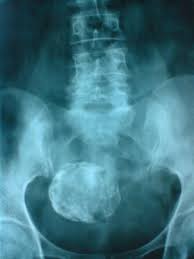

FIBROID ADA TIME USIA SUBUR

Statistik 2019 mendapati kira-kira 20 % wanita usia subur mempunyai FIBROID iaitu antara, paling kerap pada usia 30-50 tahun. Namun, sepanjang sepuluh tahun yang lalu, jumlah wanita di bawah 30 yang mengalami fibroid telah meningkat dua kali ganda.

Lebih kurang 3% daripada penghidap FIBROID mempunyai masalah kesukaran untuk hamil. Ini kerana kehadiran FIBROID akan mengubah dinding rahim dan menyebabkan kesukaran untuk perlekatan embrio pada dinding rahim. Sekiranya fibroid itu terlalu besar, ia juga akan menyebabkan salur fallopian tersumbat, dan menyebabkan seseorang itu sukar untuk hamil.

FIBROID sewaktu hamil boleh menyebabkan sakit dan tekanan pada pelvik dan menjadi punca kelahiran tidak cukup bulan.

Komplikasi lain termasuk anaemia disebabkan pendarahan haid yang banyak.